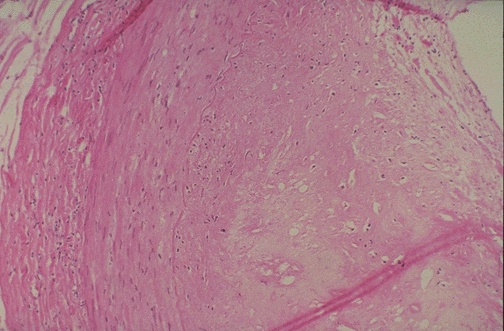

This cross section of coronary artery demonstrates the extent of the intimal plaque at the right above the internal elastic lamina.